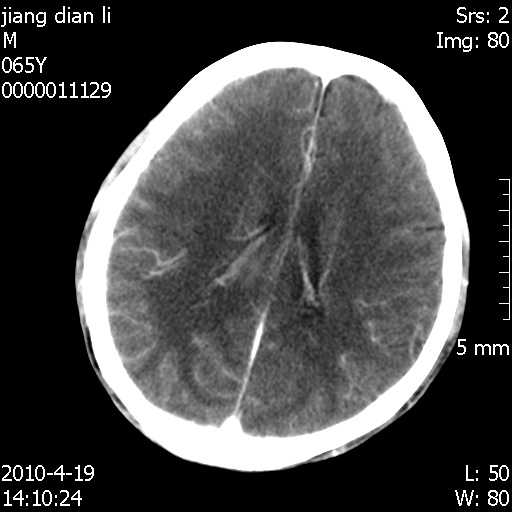

老年男性,突发左下肢无力1天,其余有价值的检查都没有。平扫ct值大约60hu,增强后ct值没什么改变,请大家讨论一下这个病例是什么?说明诊断理由。

左小脑、右大脑顶叶多发圆形高密度病灶,其周环状低密度影。考虑多发脑出血。隔期观察。

至于是出血还是微小钙化所致的高密度无法考证,三个都出血也不是一点都不可能,同一种组织学类型的肿瘤受到同一个外来的因素影响后会表现出相同的病理变化。说实在的,我本身支持转移瘤的,就是想不通为什么不强化?我认为单纯脑出血的边缘不会那么光滑,并且那也不是出血的常见部位,多发也不常见。

刚刚复习了转移瘤的不典型ct征象,有4条,分享给大家:

1、高密度灶:多为瘤内有较多沙粒体钙化所致,而不是出血,ct值可高达95hu;

2、无强化;

3、无水肿;

4、无占位效应。